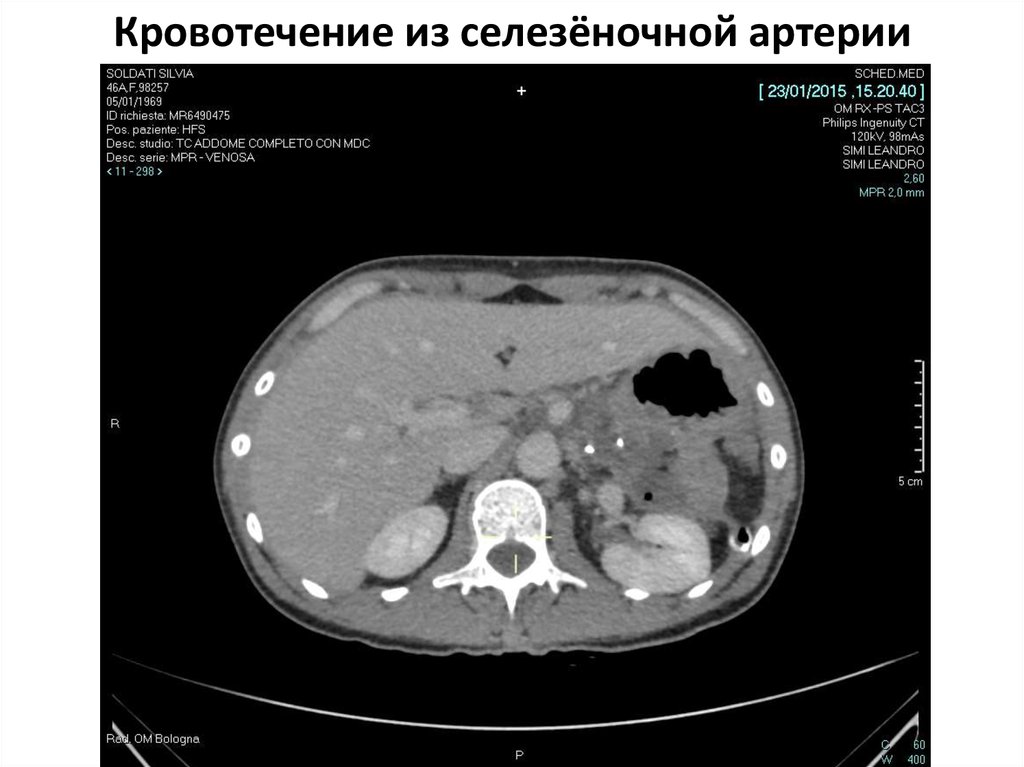

Селезеночный индекс на кт 104 фотографий